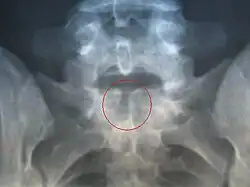

Spină bifidă ocultă

Este forma cea mai ușoară(ascunsă) a spinei bifide.[1] La această afecțiune, cum se vede și în imaginea radiografiei, partea exterioară a vertebrelor nu este complet sudată.[2] Despicătura dintre vertebre este atât de măruntă încât măduva spinării nu herniază. Pielea în zona leziunii poate să apară normală dat poate să crească și câteva fire de păr sau să apară un nev.[3]

Cele mai multe persoane cu această afecțiune nu află niciodată de existența ei, fiind în cele mai multe cazuri asimptomatic, coloana vertebrală fiind adesea neafectată.[3] Incidența spinei bifide oculte este de aproximativ 10% din populație,[4]